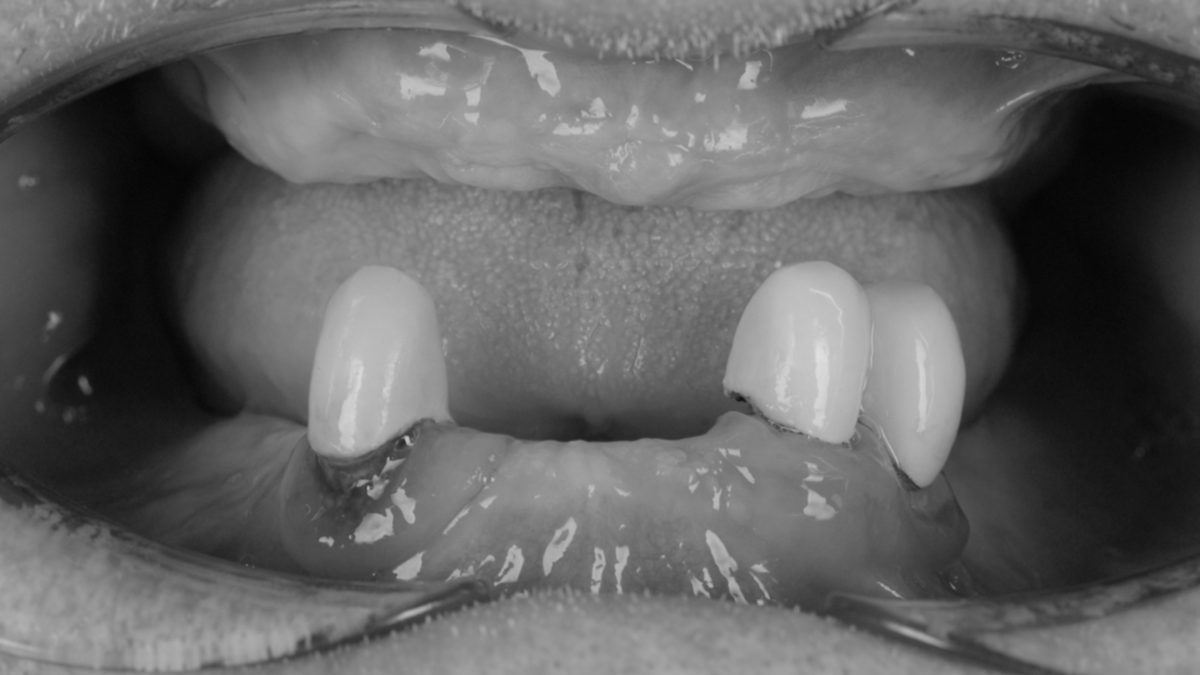

Вот с такой скромной коллекцией зубов мужчина появился у нас. Она скрывалась под съемным протезом.

Протез изначально не доставлял особого дискомфорта, но и те ощущения, которые он дарил, приятными пациент назвать на мог. Оставшиеся в наличии зубы держались на честном слове и начали болеть - продолжать использовать протез и не предпринимать никаких действий стало невозможно.